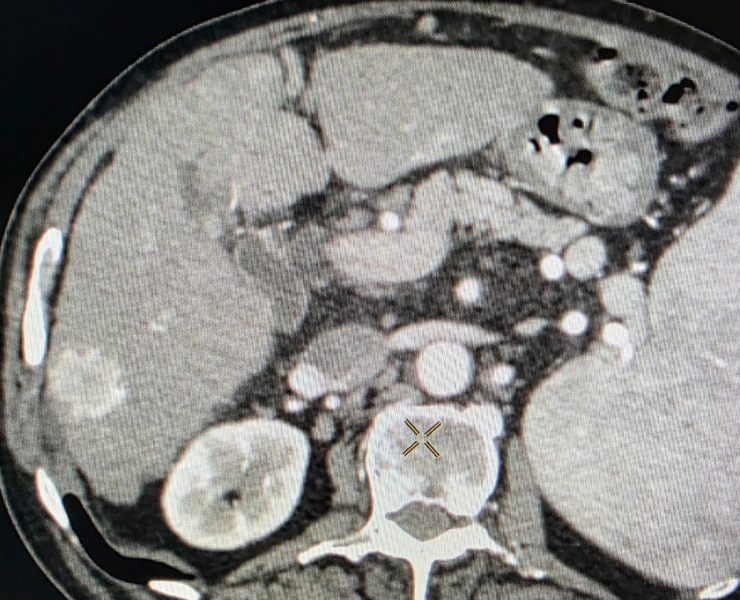

Liver Cancer Treatment

Many liver cancer patients are not suitable for surgery because of tumour location, multiple lesions, underlying liver disease or general health. In such cases, interventional radiological procedures can offer effective, targeted options:

- Thermal ablation (radiofrequency or microwave): destroys tumour tissue by heating it from within through a thin needle placed under USG/CT guidance.

- Chemoembolization (TACE): delivers chemotherapy directly into the tumour’s blood supply, followed by embolic particles to block the vessels and cut off nutrition to the cancer.